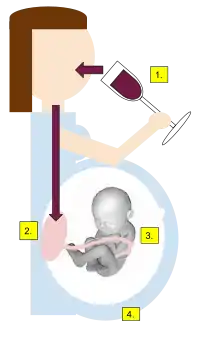

Fetal alcohol spectrum disorders are caused by a mother drinking alcohol during pregnancy.[1] Surveys from the United States found that about 10% of pregnant women drank alcohol in the past month, and 20% to 30% drank at some point during the pregnancy.[10] About 3.6% of pregnant American women are alcoholics.[11] The risk of FASD depends on the amount consumed and the frequency of consumption as well as at what point in pregnancy the alcohol was consumed.[10] Other risk factors include older age of the mother, smoking, and poor diet.[12][10] There is no known safe amount or time to drink alcohol during pregnancy.[1][13] While drinking small amounts does not cause abnormalities in the face, it may cause behavioral issues.[11] Alcohol crosses the blood–brain barrier and both directly and indirectly affects a developing baby.[14] Diagnosis is based on the signs and symptoms in the person.[1]

A human fetus appears to be at triple risk from maternal alcohol consumption:[43][44]

- The placenta allows free entry of ethanol and toxic metabolites like acetaldehyde into the fetal compartment. The so-called placental barrier is practically absent with respect to ethanol.

- The developing fetal nervous system appears particularly sensitive to ethanol toxicity. The latter interferes with proliferation, differentiation, neuronal migration, axonic outgrowth, integration, and fine-tuning of the synaptic network. In short, all major processes in the developing central nervous system appear compromised.

- Fetal tissues are quite different from adult tissues in function and purpose. For example, the main detoxicating organ in adults is the liver, whereas the fetal liver is incapable of detoxifying ethanol, as the ADH and ALDH enzymes have not yet been brought to expression at this early stage. Up to term, fetal tissues do not have significant capacity for the detoxification of ethanol, and the fetus remains exposed to ethanol in the amniotic fluid for periods far longer than the decay time of ethanol in the maternal circulation. The lack of significant quantities of ADH and ALDH means that fetal tissues have much lower quantities of antioxidant enzymes, like SOD, glutathione transferases, and glutathion peroxidases, resulting in antioxidant protection being much less effective.